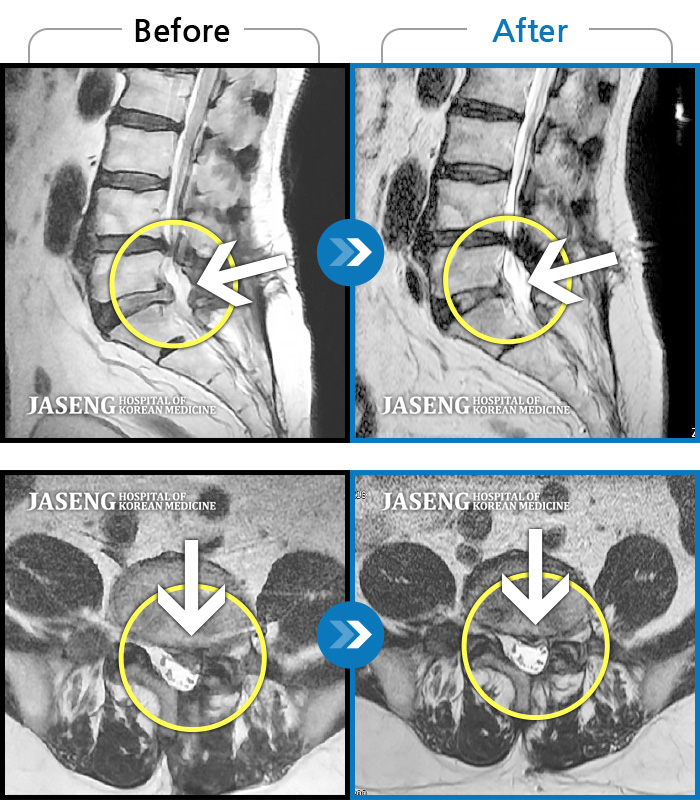

ȯںп  Ǹ   ǿ ԿǾ, ο  ġ  ۿ     Ƿ   ġḦ Ͻñ ٶϴ.